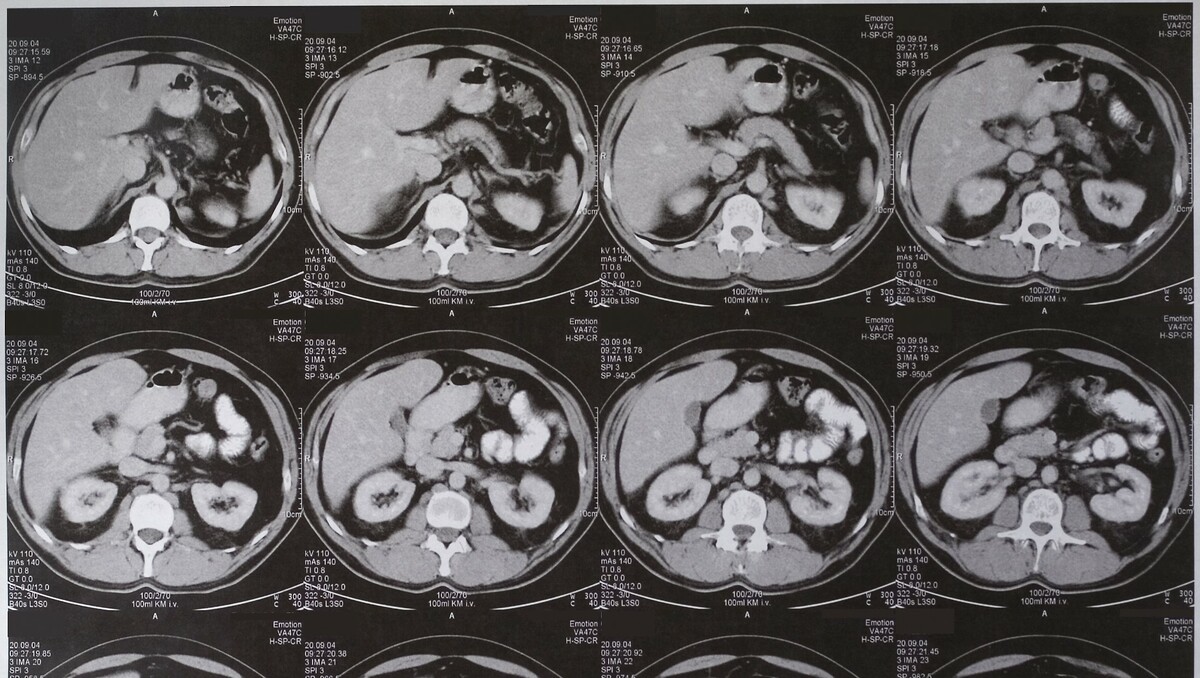

CT: Abdomen/Pelvis

What is a CT scan of the abdomen and pelvis?

A CT scan of the abdomen and pelvis is a type of scan that uses special equipment to take pictures from different angles. These pictures are fed into a computer, which combines them to produce a series of cross sections or slices through the part of the pelvis being scanned. This creates a very detailed image of the abdomen and pelvis

Why might my doctor recommend a CT of my abdomen and pelvis?

Your doctor might recommend a CT scan of the abdomen and pelvis to help detect or rule out several conditions, including:

• Cysts

• Abscesses

• Infection

• Tumors

• Aneurysms

• Enlarged lymph nodes

• Foreign objects

• Bleeding into the abdominal cavity

• Diverticulitis

• Inflammatory bowel disease

• Appendicitis

• Cancer in the abdominal organs or lymph nodes.